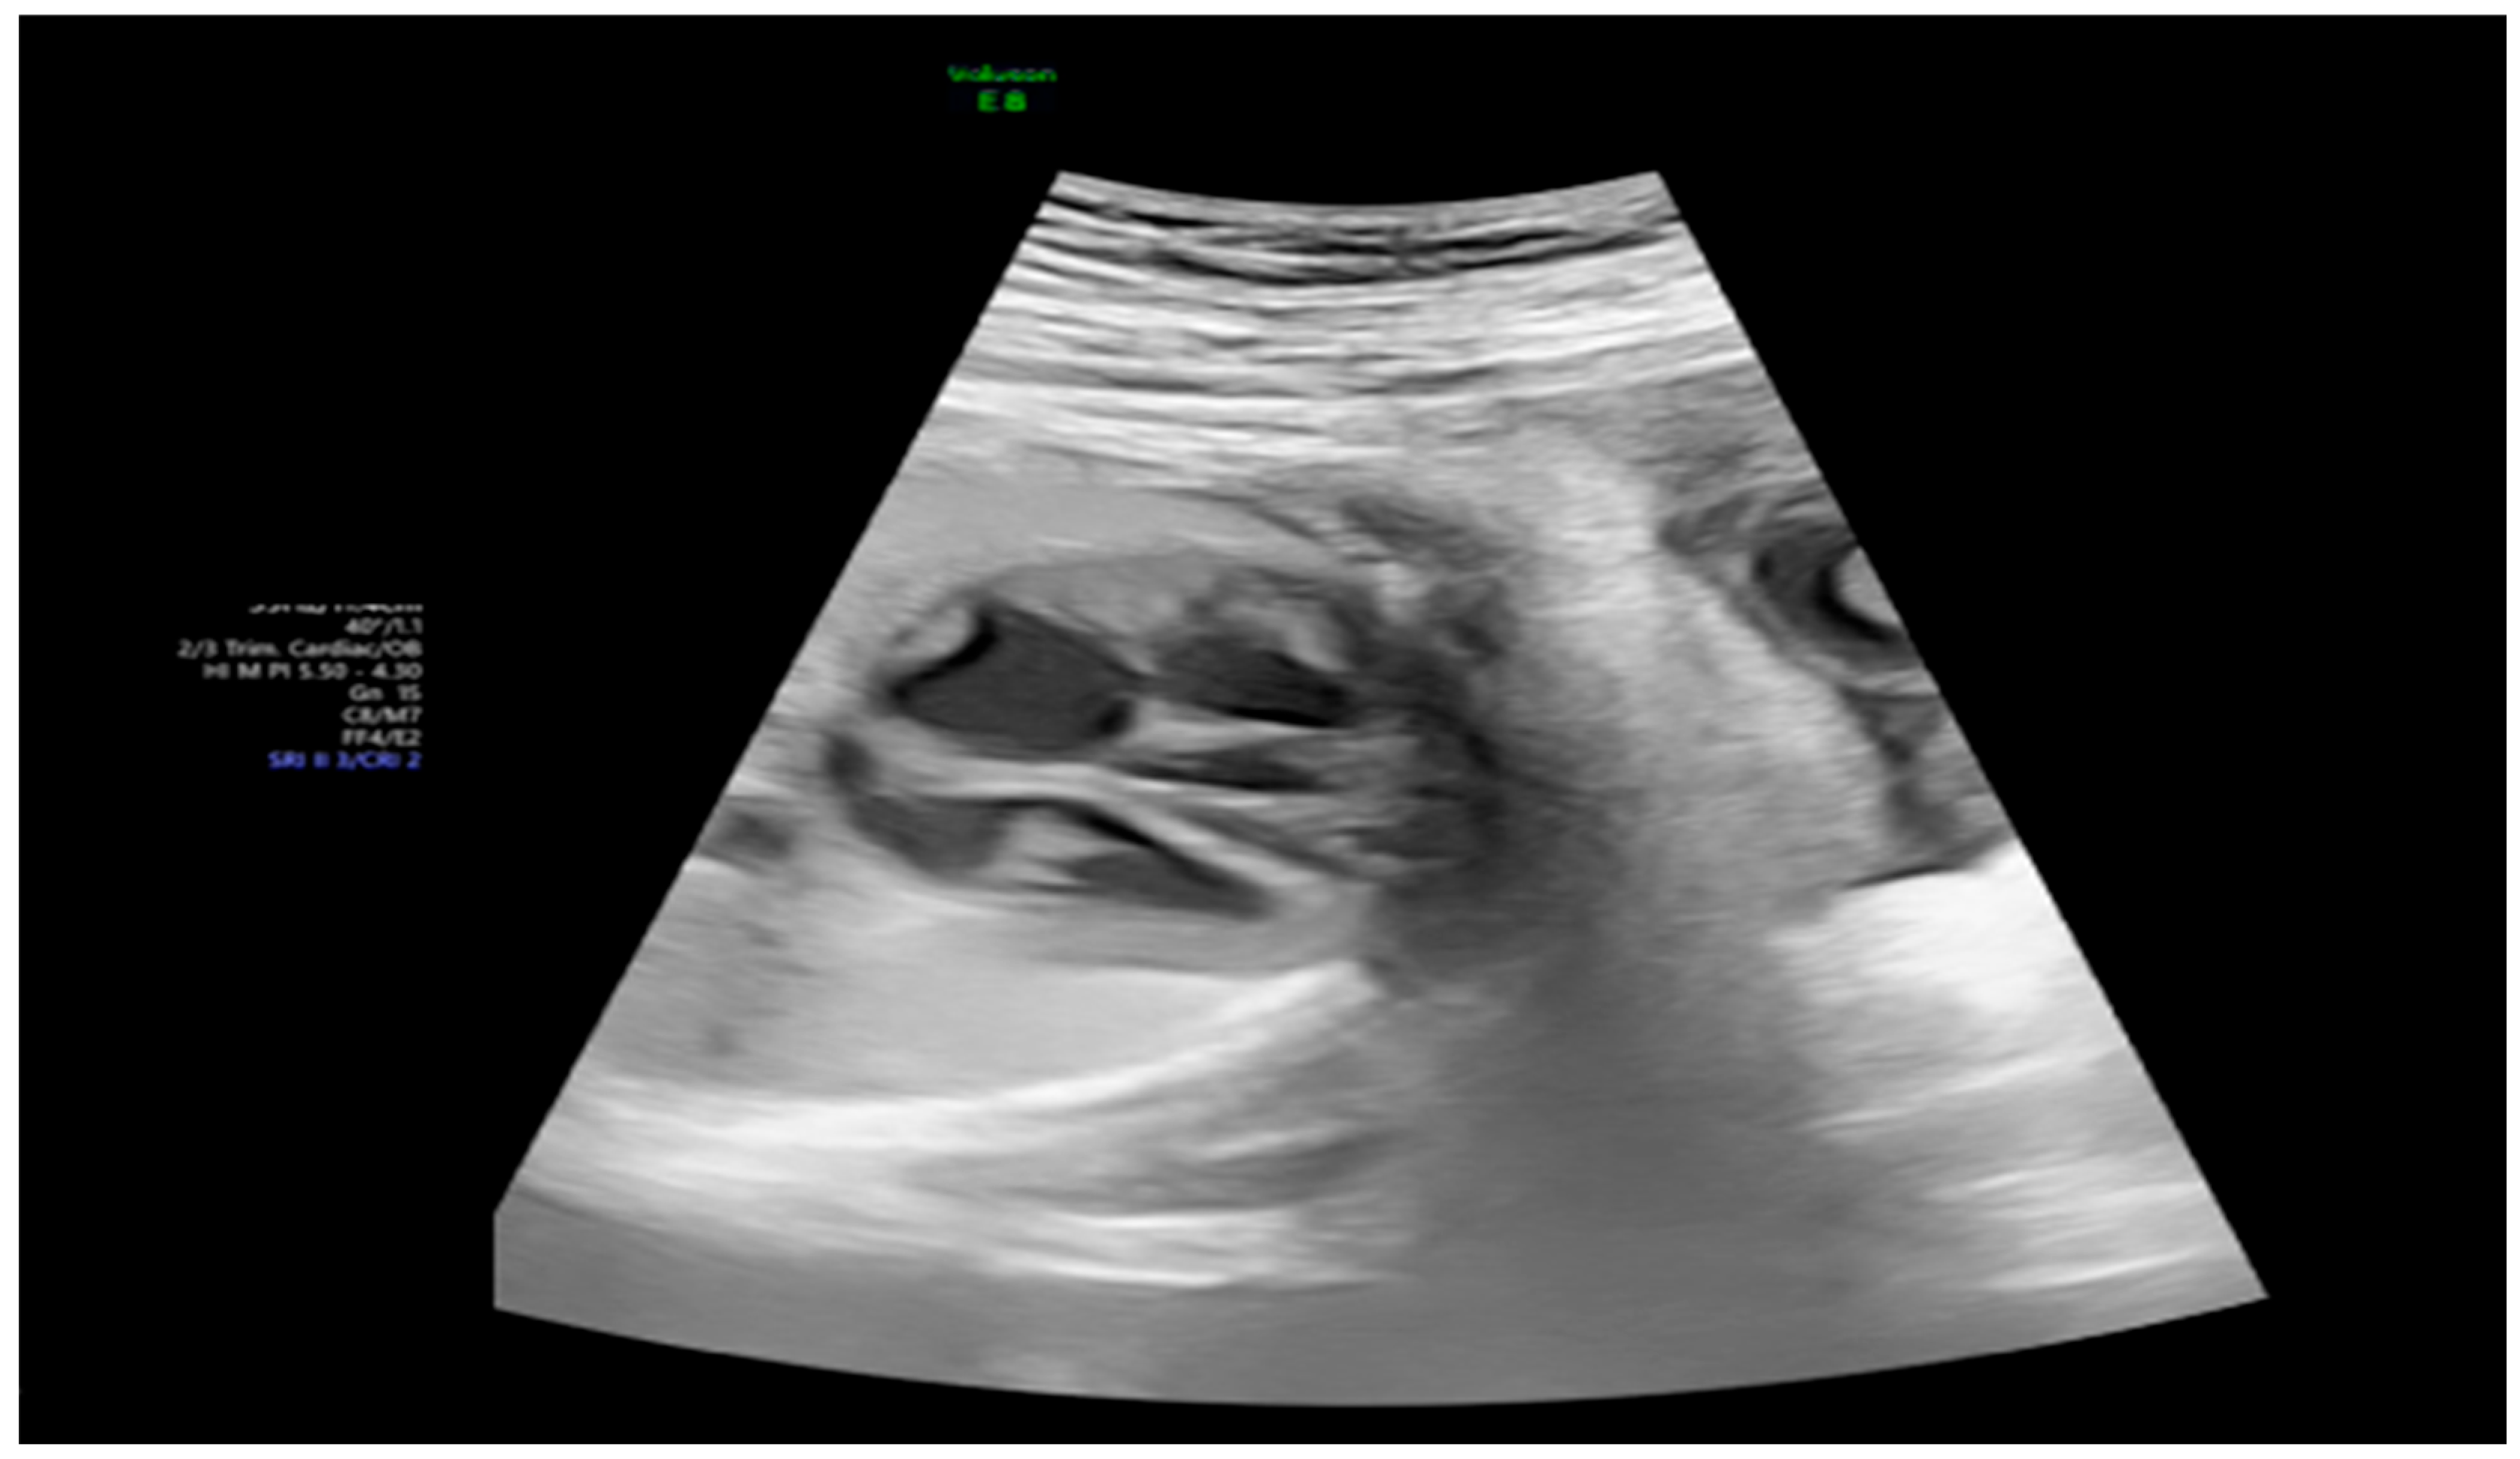

| 26 + 0 | Start of dexamethasone 4 mg/day | 60 | SF increased from 34% to 47%, but qualitative contractility decreased | Mild edema; no beta- agonists used |

| 28 + 0 | First IVIG cycle (65 g total) | 75 | SF increased to 52%; mild improvement in contractility | Initiated due to signs of fibroelastosis |

| 31 + 2 | Post-IVIG peak response | 70 | SF: 59% (LV), 52% (RV); marked biventricular improvement | Aortic isthmus 3 mm (Z-score –1.65) |

| 33 + 0 | Second IVIG cycle | 68 | Stable function maintained | Repeated full protocol; no complications |

| 36 + 3 | Delivery | 84 | – | Stable neonate; no pacemaker needed |